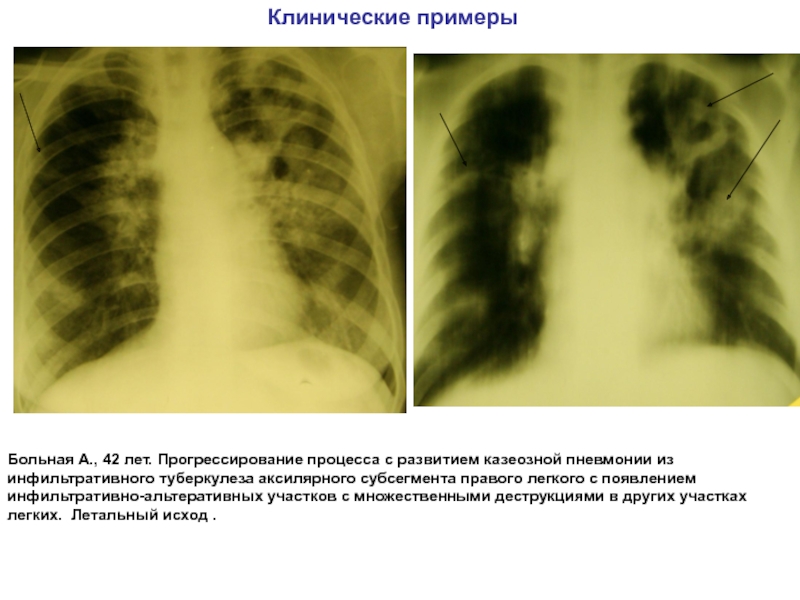

Симптомы и лечение инфильтративного туберкулеза легких

Раздел: Снимки-откровения